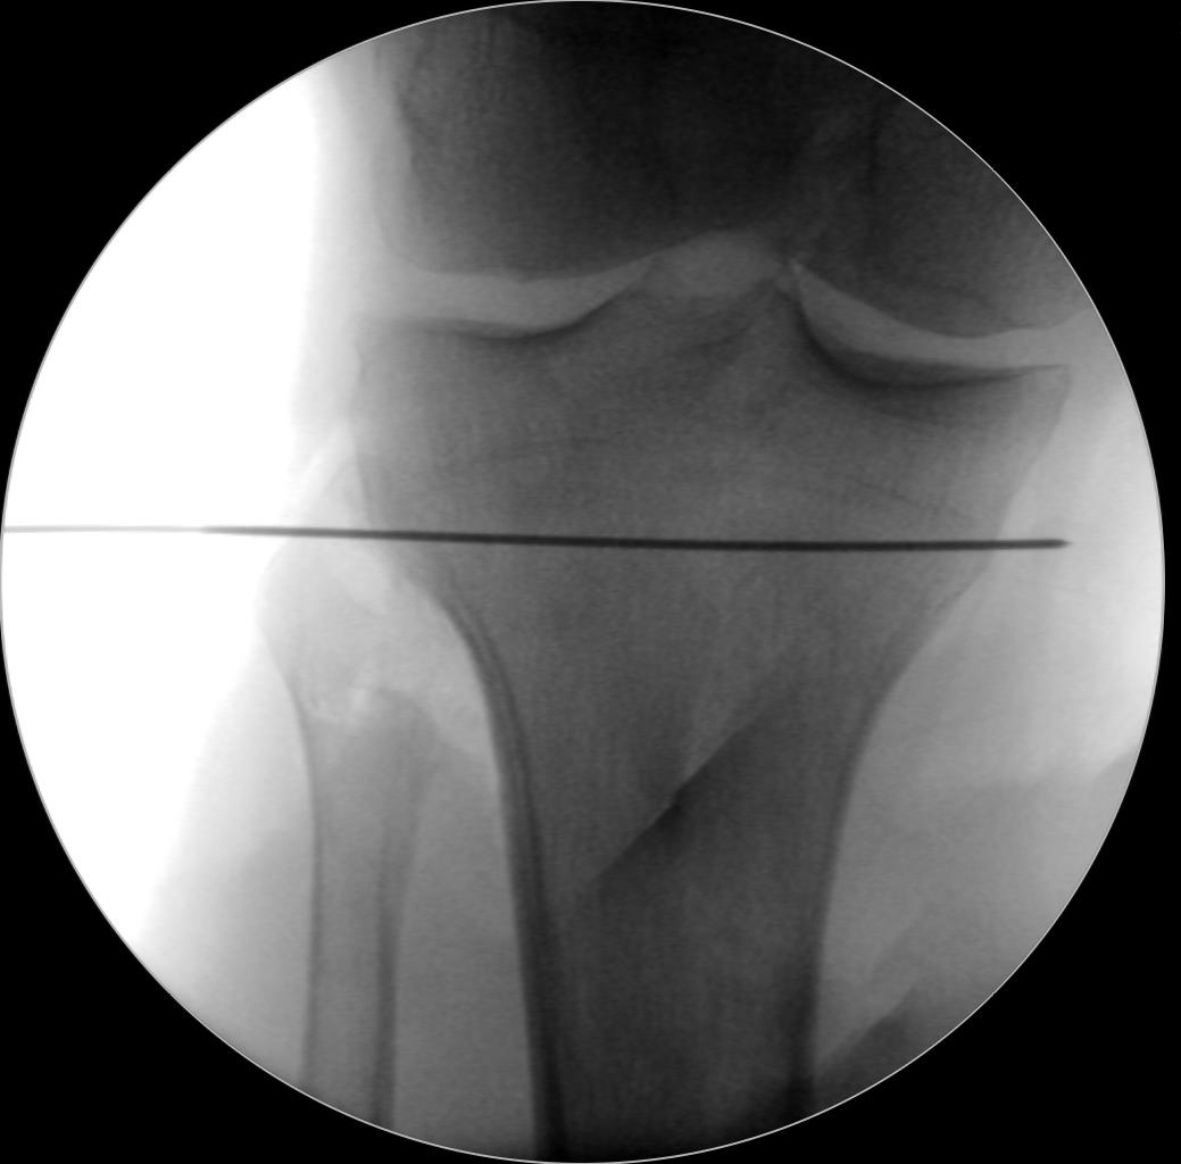

At this point, the level of the torsional osteotomy is defined by a k-wire (2 mm). The osteotomy needs to be exactly parallel to the joint line in the coronal and sagittal planes to avoid a second deformity in the frontal plane by an oblique osteotomy (Figure 6). To achieve a better control over the sagittal plane, it is recommended to position 2 k-wires in the first cases parallel to the tibial slope. However, in experienced hands this is not always necessary.

To ensure intraoperative torsional control, two 5mm-Schanz pins are placed proximally and distally to the level of the osteotomy with the desired angulation correction value.

The proximal pin is placed perpendicular to the tibial axis and the distal screw in an oblique position exactly in the torsional angle planned (Figure 7). The objective is that at the end of the derotation step, both pins will end up parallel to each other.